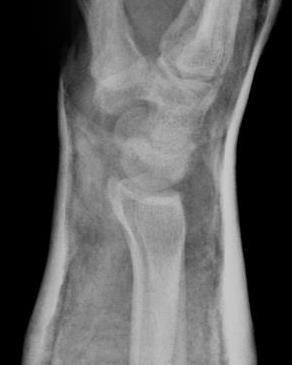

Gilula carpal arcs

Normally there are 3 smooth carpal arcs on PA xray

Arc I: Proximal cortical margins of proximal carpal row Arc II: Distal carpal margin of the proximal carpal row Arc III: Proximal cortices of the capitate and hamate |

AP X-ray

Disruption of Gilula's 3 smooth carpal arcs / triangular lunate

Normal versus disruputed Gilula's carpal arcs

Piece of pie / triangular appearance of lunate